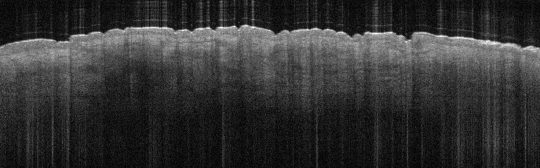

VA9: Left Forearm, Adjacent Normal